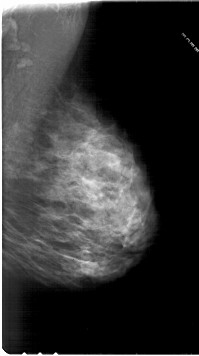

A_1814_1.RIGHT_MLO

RIGHT_MLO LINES 6751 PIXELS_PER_LINE 3781 BITS_PER_PIXEL 12 RESOLUTION 43.5 NON_OVERLAY